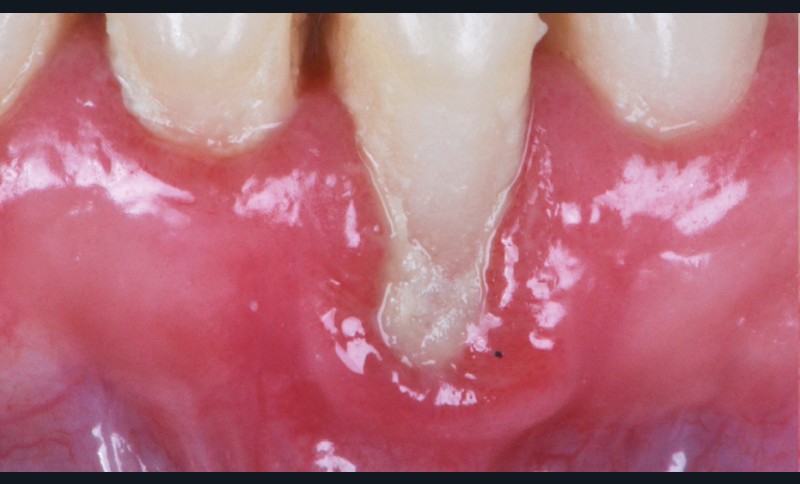

Les facteurs prédisposants combinés aux causes directes traumatiques ou inflammatoires contribuent à l’apparition de récession. Ces facteurs sont : le phénotype fin, la proéminence radiculaire (fig. 4), la malposition dentaire (fig. 5), le traitement orthodontique et les insertions de freins…